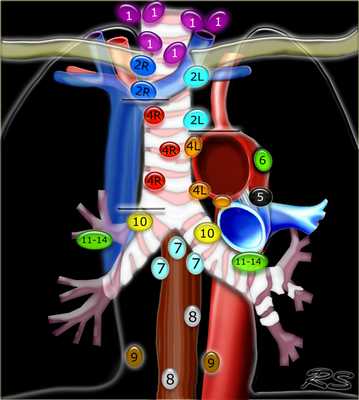

Лимфатические узлы средостения

Лимфатические узлы 3 группы не примыкают к трахее в отличии от лимфатических узлов 2 группы. Они подразделюятся на: 3А кпереди от сосудов 3Р позади пищевода/превертебрально Они не доступны при медиастиноскопии. 3Р группа может быть доступна при чреспищеводной эхокардиографии.

4R. Правые нижние паратрахеальные лимфатические узлы

- Верхняя граница: пересечение нижнего края левой плечеголовной вены с трахеей.

- Нижняя граница: нижний края непарной вены. 4R узлы распространяются до левого края трахеи.

4L. Левые нижние паратрахеальные лимфатические узлы

4L узлы расположенные слева от левой стенки трахеи, между горизонтальными линиями проведенными касательно верхней стенке дуги аорты и линией проходящей через левый главный бронх на уровне верхнего края верхнедолевого бронха. Они включают паратрахеальные узлы расположенные кнутри от артериальной связки.

Узлы 5 группы (аортопульмонального окна) расположены кнаружи от артериальной связки.

На левом изображении над уровнем легочного ствола представлены нижние паратрахеальные узлы слева и справа, так же здесь представлены узлы 3 и 5 групп.

Изображение слева выше уровня карины. Слева от трахеи 4L узлы. Обратите внимание что они расположены между легочным стволом и аортой, но не в аортопульмональном окне, потому что они лежат медиальнее артериальной связки. Лимфатические узлы латеральнее легочного ствола относятся к 5 группе.

- 5. Субаортальные лимфатические узлы

- Субаортальное или аортопульмональное окно расположено кнаружи от артериальной связки и проксимальнее первой ветви левой легочной артерии и лежит в пределах медиастинальной плевры.

- Парааортальные лимфатические узлы лежат кпереди и кнаружи от восходящего отдела аорты и между верхним и нижним краями дуги аорты.

7. Подкаринальные лимфатические узлы

Эти лимфатические узлы расположены ниже уровня бифуркации трахеи (карины), но не относятся к нижнедолевым бронху и артерии. Справа они располагаются каудальнее нижней стенки промежуточного бронха. Слева они располагаются каудальнее верхней стенки нижнедолевого бронха. Слева лимфатический узел 7 группы справа от пищевода.

8. Параэзофагеальные лимфатические узлы

Эти лимфатические узлы ниже подкаринальных лимфатических узлов и распространяются каудальнее до диафрагмы. На изображении слева ниже уровня карины справа от пищевода обозначен лимфатический узел 8 группы.

9. лимфатические узлы легочной связки

Данные лимфатические узлы лежат в пределах легочной связки, в том числе и по ходу нижней легочной вены. Легочная связка представлена дупликатурой медиастинальной плевры охватывающей корень легкого.

10. лимфатические узлы корня легкого

Лимфатические узлы корня расположены проксимальнее долевых узлов, но дистальнее медиастинальной дупликатуры и узлов промежуточного бронха справа.

Все лимфатические узлы 10-14 групп являются N1 узлами, так как они находятся вне средостения.

1. лимфатические узлы вырезки грудины видны только на этом уровне и выше него

2. верхние паратрахеальные лимфатические узлы: ниже ключиц , справа над пересечением нижнего края левого плечеголовного ствола и трахеи, а слева над дугой аорты

3. Преваскулярные и ретротрахеальные: кпереди от сосудов (3А) и превертебральные (3Р)

4. Нижние паратрахеальные: ниже верхнего края дуги аорты до уровня главного бронха

5. Субаортальные (аортопульмональное окно): лимфатические узлы кнаружи от артериальной связки или кнаружи от аорты или левой легочной артерии.

6. Парааортальные: узлы лежащие кпереди и кнаружи от восходящего отдела аорты и дуги аорты под верхним краем дуги аорты.

7. Субкаринальные лимфатические узлы.

8. Параэзофагеальные лимфатические узлы (ниже карины).

9. Лимфатические узлы легочной связки: лежат в пределах легочной связки.